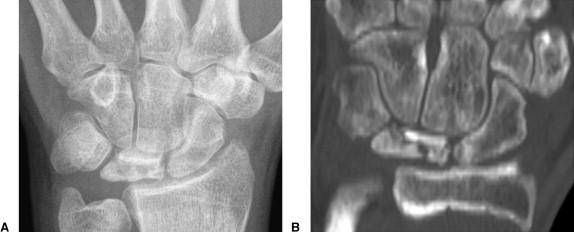

Lunate 의 sclerosis가 발견되면 Stage II 이며 Joint leveling 이 핵심입니다. ulna 변위가 중립 혹은 양성인 경우에는 radial wedge osteotomy나 그 외의 치료를 시행해 볼 수 있습니다.

Stage III 부터는 주상골도 영향을 받기 시작하며 회전을 하거나(IIIA, cortical ring 관찰가능), carpal height 가 줄어드는 것을 확인할 수 있습니다. (IIIB), IIIA 까지는 II와 치료를 거의 동일하게 하지만, IIIB 부터는 Proximal row carpectomy 나 STT, SC fusion 등을 시행해 볼 수 있습니다.